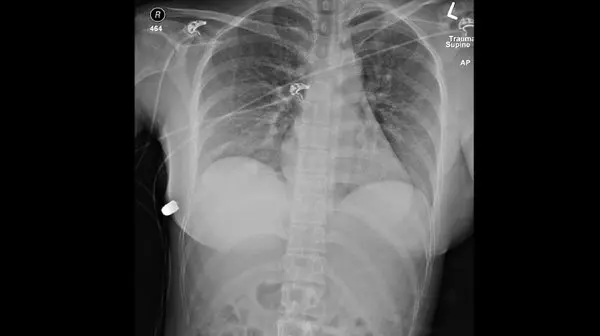

گزارش رسانه های کانادا حاکی از آن است که زن 30 ساله پس از شلیک گلوله به سینه اش متوجه خونریزی در آن ناحیه شد که با مراجعه به بیمارستان پزشکان متوجه شدند که گلوله به ایمپلنت سلیکونی سینه قربانی برخورد کرده که خوشبختانه جانش را از مرگ نجات داده است.

برخورد گلوله با پروتز سینه زن کانادایی

پزشکان با خارج کردن سلیکون از سینه این زن تجویز آنتی بیوتیک کرده تا از عفونت جلوگیری شود و از او خواستند تا مدتی از گذاشتن پروتز جدید جلوگیری کند.